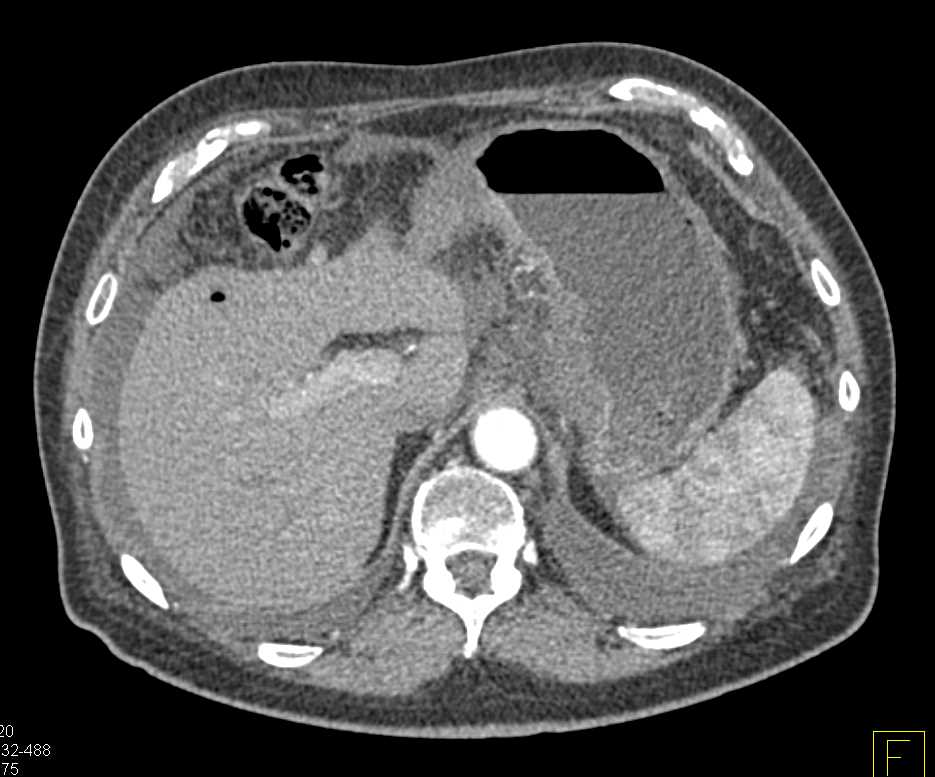

Gastric Cancer with Carcinomatosis